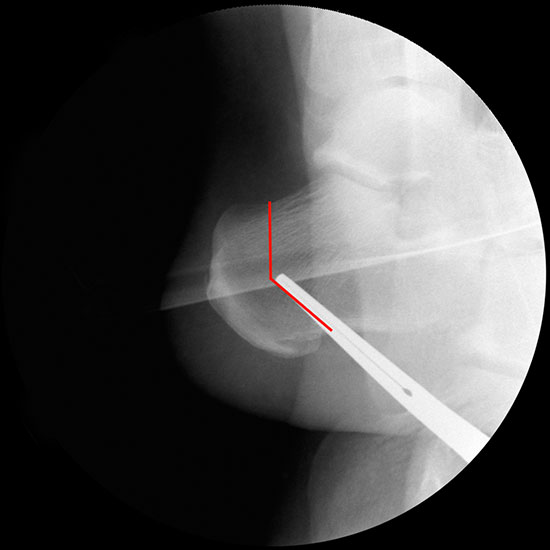

Bei Rückfussfehlstellungen ist meist eine knöcherne Korrektur des Kalkaneus indiziert. Dabei wird das Fersenbein im Bereich des Tuber calcanei durchtrennt und der Achillessehnenansatz nach medial oder lateral geschoben. Zusätzlich ist eine Rotation des Tuber möglich, wodurch sich der Korrektureffekt noch verstärkt. Durch die Wahl der Osteotomieebene kann die Verscheibung mit einer Verlängerung oder Verkürzung des Fersenbeins kombiniert werden. Die Osteosynthese erfolgt typischerweise durch perkutan eingebrachte Schrauben.

Durch eine V-förmige Schnittführung kann eine Translation des Tuber calcanei nach dorsal zuverlässig verhindert werden, bei hoher primärer Stabilität.

Bildwandler Bildgebung.

Bildverstärker.